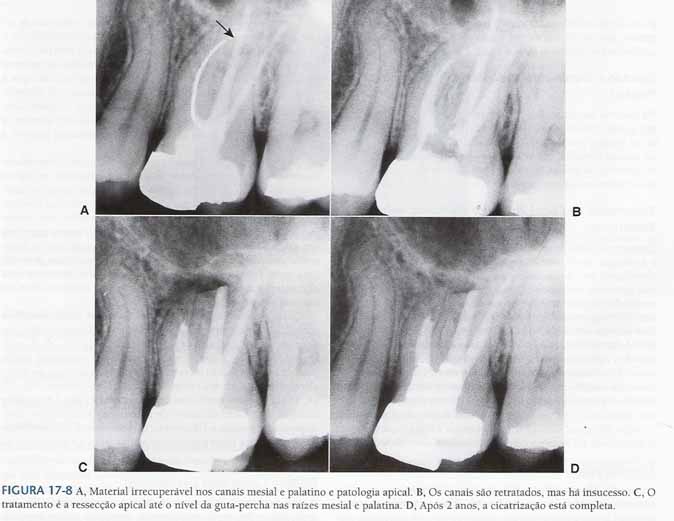

Material irrecuperável

impedindo o tratamento ou retratamento de canal

Material Irrecuperável Dentro do Canal

Canais ocasionalmente são bloqueados por objetos como instrumentos fraturados, materiais restauradores, segmentos de pinos, ou outros objetos estranhos.

Se houve evidência de patologia apical, esses materiais podem ser removidos cirurgicamente, em geral com uma parte da raiz.